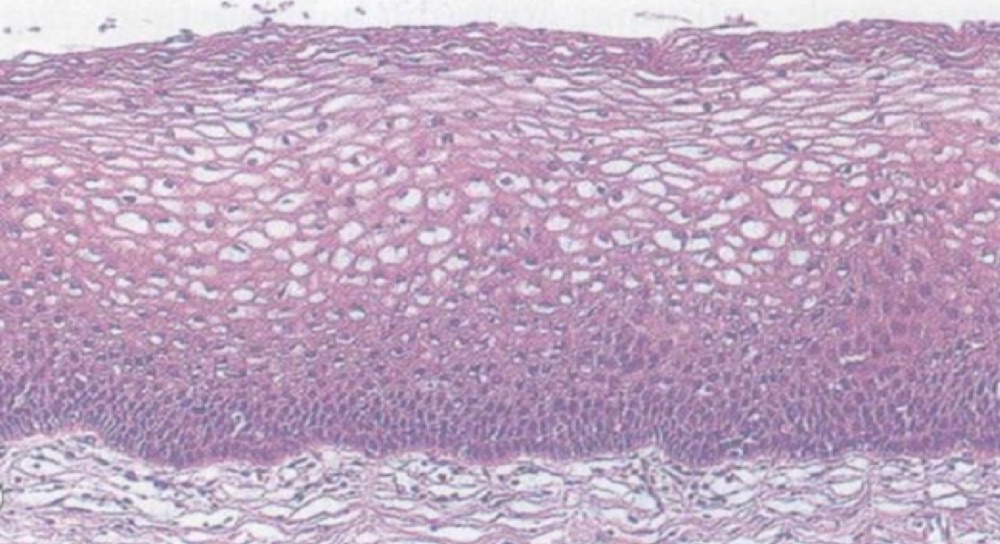

1 Tissue ประเภทใด

5 จากภาพเป็นเนื้อเยื่อชนิดใด

6 จงบอกชนิดของเนื้อเยื่อ

12 จากภาพคือ เนื้อเยื่อชนิดใด

13 จากภาพ คือเนื้อเยื่อใด

14 เนื้อเยื่อชนิดใด